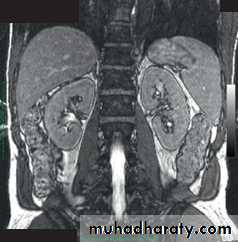

MRI images of the kidneys. A Normal kidneys. B Polycystic kidneys; although the kidney enlargement is extreme.

A

B